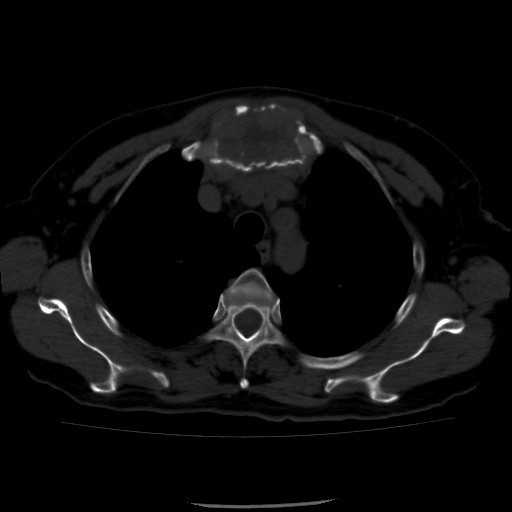

诊断:甲状腺恶性肿瘤(术后);手术后甲状腺功能减退。 治疗:入院时甲状腺球蛋白>455pmol/L,甲状腺素2.793uIU/ml,根据病情于2014-6-3予大剂量碘-131 100mCi清甲治疗;2014年6月全身碘扫示:全身多发异常摄碘组织,考虑甲状腺癌术后双侧甲状腺组织及锥状叶残留并全身多发骨转移。2014年9月胸部CT示:1、双肺多发转移瘤,并胸骨转移;胸1、8、10、腰1椎体内多发结节灶,考虑转移瘤可能性大。2、右肺中叶内侧段、双肺下叶散在慢性炎症。2014年12月全身碘扫:1.全身多处异常摄碘组织,考虑多发骨转移瘤。又于2014年12月复查甲状腺球蛋白抗体90.400U/mL,促甲状腺素6.914uIU/ml。遂于2014-12-22口服250mCi大剂量放射性碘-131。治疗后全身碘扫复查结果提示:2.左肺下叶摄碘组织,不排除转移瘤,建议进一步检查。与2014.6.6检查相比,颈部甲状腺部位放射性浓集灶消失,余病灶放射性浓集程度较前稍降低。

患者又于2015年10月胸部CT复查,结果提示:1、甲癌术后改变;双肺多发转移瘤,大部分病灶较前缩小,左肺下叶病灶较前增多,部分较前增大;胸骨转移;胸1、8、10、腰1椎体内多发结节灶,基本同前,考虑转移瘤可能性大。2、右肺中叶内侧段、左肺上叶舌段及双肺下叶散在慢性炎症。